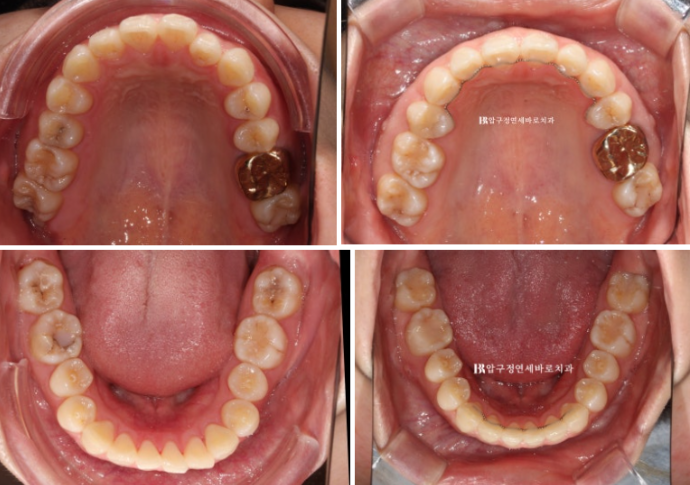

This is the state with all retainers in place.

Let’s look at the before-and-after comparison photos.

Improvement in the midline and overbite

The goal of treatment is a tight, seamless bite.

As the upper front tooth protrusion was resolved, the gap between the upper and lower front teeth decreased.